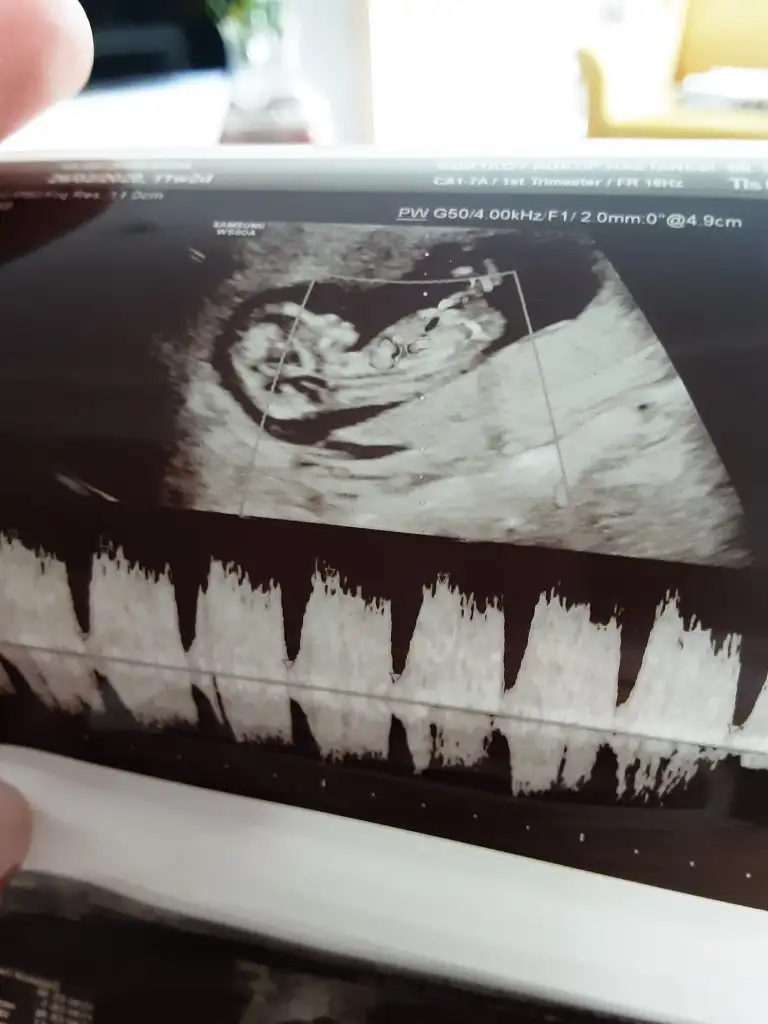

13+4 sizce kız mı erkek mi?